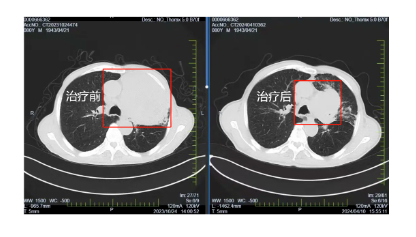

在國文醫(yī)院胸部腫瘤放化療Ⅲ病區(qū)醫(yī)護人員的精心照料和密切監(jiān)測下,患者經(jīng)過6周期的免疫治療,肺部腫瘤明顯縮小,一年間由原來的95x90mm降至70x50mm,腫瘤明顯縮小且腫瘤內(nèi)見壞死及空洞。張大爺?shù)纳眢w狀況也逐漸好轉(zhuǎn),原本因癌細胞壓迫導(dǎo)致的呼吸困難癥狀得到了明顯緩解,能夠進行一些簡單的日?;顒?,張大爺?shù)哪樕嫌种匦戮`放出笑容。